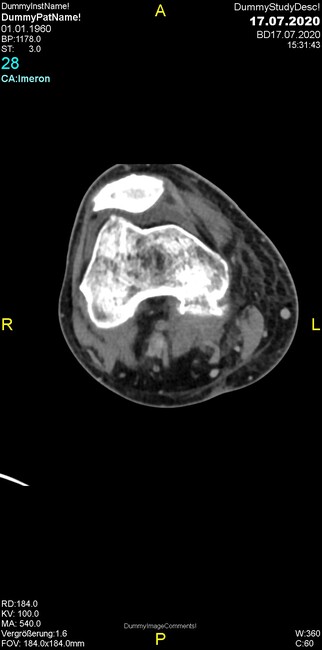

Was fällt in der CT im Knochenfenster auf?

- Mediale Gelenkspaltverschmälerung

- Dezente Erosion der fibulären Kortikalis

- Frakturspalt der lateralen Tibiametaphyse

- Weichgewebskalzifikationen lateral angrenzend an den Gelenkspalt

- Osteolyse der Tibiametaphyse unter Beteiligung der Kortikalis